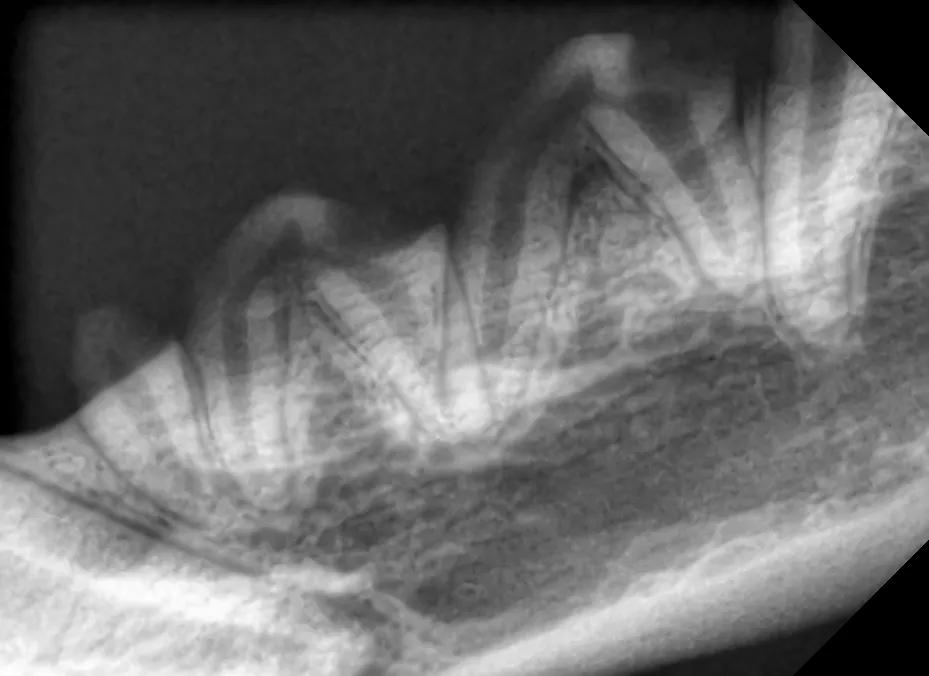

另外,彭医生还需要确认狗狗是否有牙髓疾病。这次, 彭医生用DR“拍”全口口腔X线片,为狗狗的整个口腔进行检查 。

数字化X线影像系统,简称DR。和X光拍片一样,DR也是利用X线来“扫描”小生命的身体,从而发现体内存在的问题。

但DR比普通X光拍片 更高清 ,放射线危害也相对更低,而且可以 直接数字化处理 ,效率会更高!

维特深圳动物医院还有 专门用于口腔的牙科DR ,该设备可以帮医生“拍”到更清晰的牙齿成像,让医生对牙周及牙髓疾病的评估更全面精准。

很快,DR结果出来,所幸汪兄汪弟都没有牙髓疾病,也没有牙龈炎等其他症状。

(其中一张DR检查照)